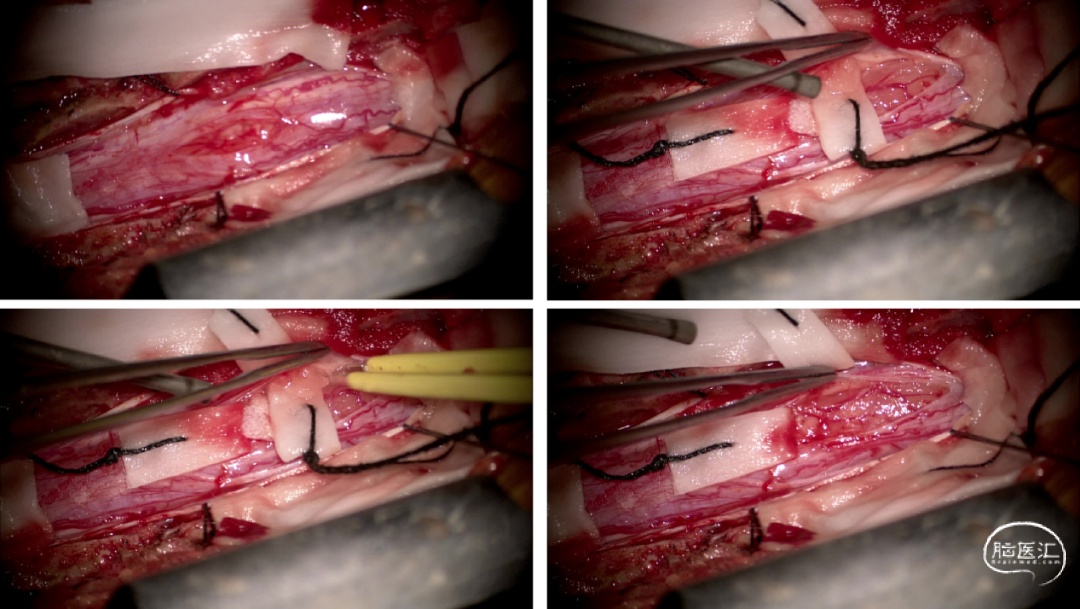

手术情况

硬脊膜张力高,脊髓向背侧膨出,与脊髓腹侧粘连紧密,肿瘤挤压脊髓,肿瘤边界分离,减少对胸髓的牵拉,降低了术后患者神经功能发生的概率,术后患者肢体麻木症状改善。